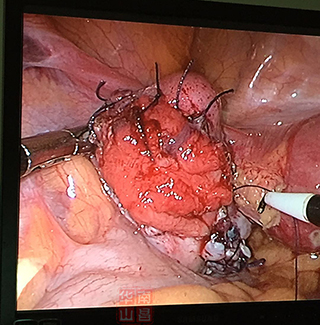

输卵管积水造口整形术后